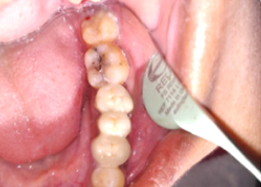

Hemisectomy

Prosthesis Cementation (Bridge)

Radiograph with Prosthesis (8 Months)